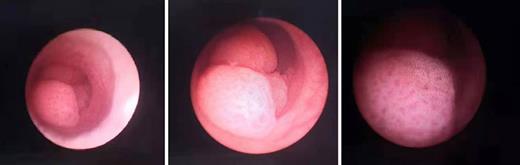

The postoperative follow-up via endoscopy and CT (the patient refused to take washings from the upper urinary tract) has been more than a year since the TURBT and ureteroscopic retrograde tumor ablation. Urethrocystoscopy has not detected neoplasm, and CT has not detected metastasis in the periodic review.